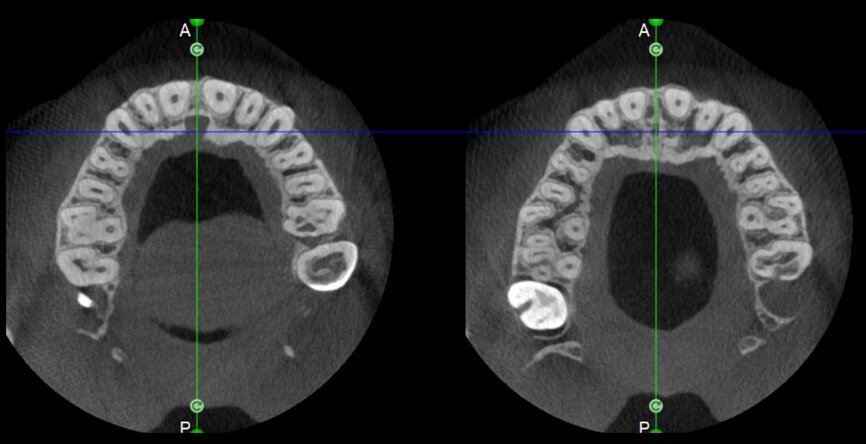

The case with which I would like to start my clinical review is a perfect example of how difficult it is to establish the origin of the patient’s symptoms on the basis of an intraoral radiograph alone. Not only does the 2D study fail to establish with certainty the presence of a lesion, but more importantly, it is impossible to establish the size, morphology and type of the lesion. An analysis of the 3D imaging, however, provides a clear picture of the clinical situation: the coronal and sagittal slices revealed the presence of a large lesion extending from the apex of the mesial root of this molar to the furcation, while the axial slices allow us to conduct a precise analysis of the endodontic anatomy and, in particular, the shape of the mesial root, which in this case was fused with the palatine root. A full overview of the case can, therefore, guide the decision-making process and direct the treatment plan towards a specific type of treatment (Figs. 1–4).